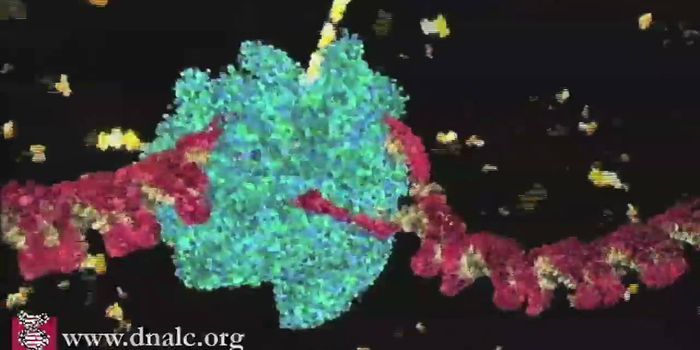

MAY 04, 2021Cell & Molecular BiologyYou can see the spike protein of the virus in action in this video.